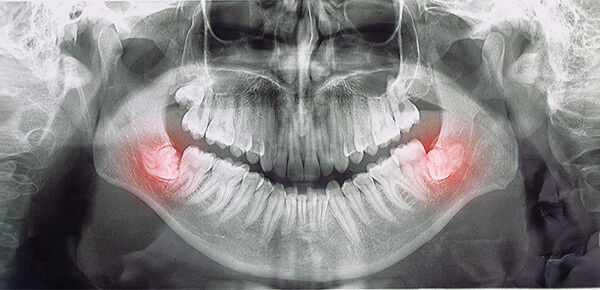

Proces usuwania ósemek rozpoczyna się od szczegółowej konsultacji stomatologicznej. Lekarz ocenia stan jamy ustnej, położenie zęba mądrości oraz wskazania do zabiegu. Niezbędnym elementem jest diagnostyka radiologiczna (RTG lub tomografia CBCT), która pozwala precyzyjnie zaplanować zabieg i dobrać odpowiednią technikę chirurgiczną.

Zabieg chirurgicznego usuwania ósemek wykonywany jest w skutecznym znieczuleniu miejscowym, co pozwala przeprowadzić procedurę w sposób komfortowy i bezbolesny dla pacjenta. Przed rozpoczęciem zabiegu lekarz dokładnie analizuje warunki anatomiczne oraz położenie zęba mądrości, aby dobrać najbardziej bezpieczną i przewidywalną technikę leczenia. W zależności od sytuacji klinicznej możliwa jest klasyczna ekstrakcja zęba lub chirurgiczne usunięcie ósemki, szczególnie w przypadku zębów zatrzymanych lub częściowo zatrzymanych w kości. Zabieg przeprowadzany jest z zachowaniem maksymalnej precyzji i delikatności tkanek, co pozwala ograniczyć uraz operacyjny oraz sprzyja prawidłowemu procesowi gojenia. Każdy przypadek traktowany jest indywidualnie, z uwzględnieniem bezpieczeństwa pacjenta, komfortu zabiegu oraz długofalowego zdrowia jamy ustnej.